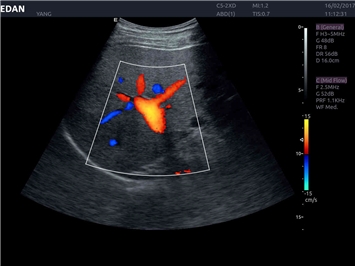

• Кардиологических исследований

Трехмерная реконструкция ЦДК:

Да

Тканевой допплер:

Кардиология: